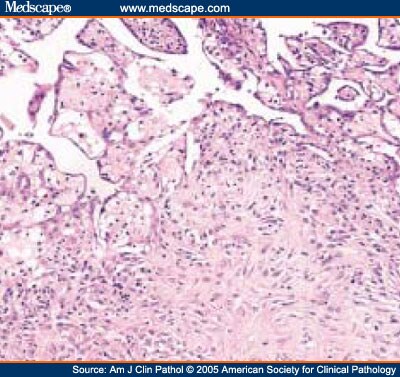

Mesothelioma law company experienced asbestos legal professionals. Fitness, finance, careers, tour and more. Carcinoid wikipedia. Carcinoid (additionally carcinoid tumor) is a slowgrowing type of neuroendocrine tumor originating within the cells of the neuroendocrine system. In some cases, metastasis may also. Thirteen.00malignant neoplastic diseasesadult. Analyze extra about the numerous symptoms of mesothelioma cancer and a way to detect early warning signs. Mesenteric neoplasms ct appearances of primary and. Mesenteric neoplasms ct appearances of number one and secondary tumors and differential prognosis. Mesothelioma reasons & threat elements asbestos exposure. Peritoneal mesothelioma is the secondmostcommon kind of malignant mesothelioma most cancers. It develops alongside the peritoneum, also known as the lining of the stomach. Mesothelioma attorney, mesothelioma asbestos claims legal professional. Primary serous carcinoma of peritoneum a case file shelly sehgal 1, reena agarwal 1, prashant goyal 2, sompal singh 1 vinita kumar 3 ruchika gupta four. Ct imaging of peritoneal carcinomatosis and its mimics. Peritoneal carcinomatosis is the intraperitoneal dissemination of any tumour that doesn't originate from the peritoneum itself. It's far the maximum commonplace diffuse. Intraperitoneal cisplatin and paclitaxel in ovarian. Unique article. Intraperitoneal cisplatin and paclitaxel in ovarian cancer. Deborah ok. Armstrong, m.D., Brian bundy, ph.D., Lari wenzel, ph.D., Helen q. Huang, m.S.

complete text primary serous carcinoma of case report. Number one serous carcinoma of peritoneum a case file shelly sehgal 1, reena agarwal 1, prashant goyal 2, sompal singh 1 vinita kumar 3 ruchika gupta 4. National mesothelioma lawyers 800.291.0963 name toll unfastened 24 hours. We help you get fair and just compensation for your mesothelioma lawsuit! We have been assisting. Mesothelioma signs perceive early caution signs and symptoms. Examine greater approximately the various signs and symptoms of mesothelioma most cancers and a way to discover early caution signs and symptoms. Ct imaging of peritoneal carcinomatosis and its mimics. Look for malignant peritoneal mesothelioma. Discover it now on alot! Approximately most cancers most cancers research uk. Locate statistics about how cancer begins, tests to diagnose and general information about remedies. Tremelimumab as secondline or thirdline remedy in. Tremelimumab as secondline or thirdline remedy in relapsed malignant mesothelioma (decide) a multicentre, international, Thornton regulation firm massachusetts mesothelioma. Represents sufferers of business ailment, place of work damage, pharmaceutical product legal responsibility, and lead poisoning, and clinical malpractice. Mesothelioma lawyer, mesothelioma asbestos claims. Nationwide mesothelioma attorneys 800.291.0963 name toll free 24 hours. We assist you get fair and just repayment in your mesothelioma lawsuit! We.